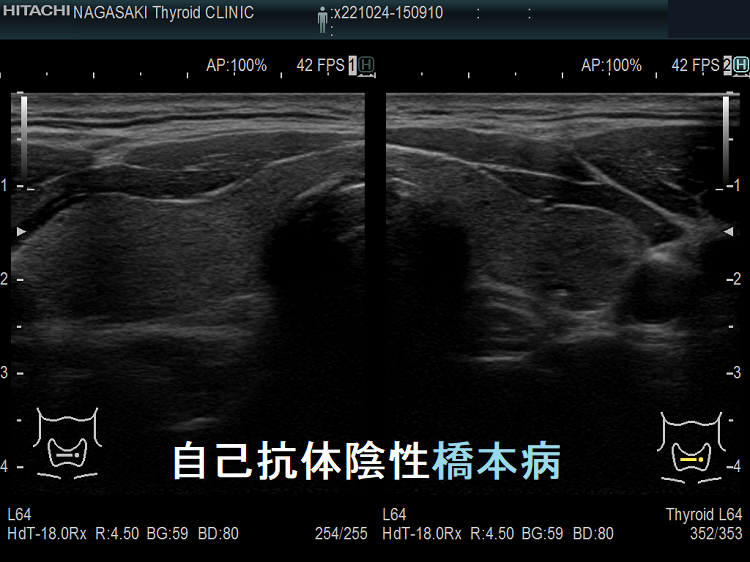

自己抗体陰性橋本病

自己抗体陰性橋本病 超音波(エコー)画像;実は、抗サイログロブリン抗体(TgAb)、抗甲状腺ペルオキシダーゼ抗体(TPOAb)陰性の橋本病が、かなりの割合で存在します。特に、これらの抗体が上昇する前の20-30代の若年女性で多い印象です。